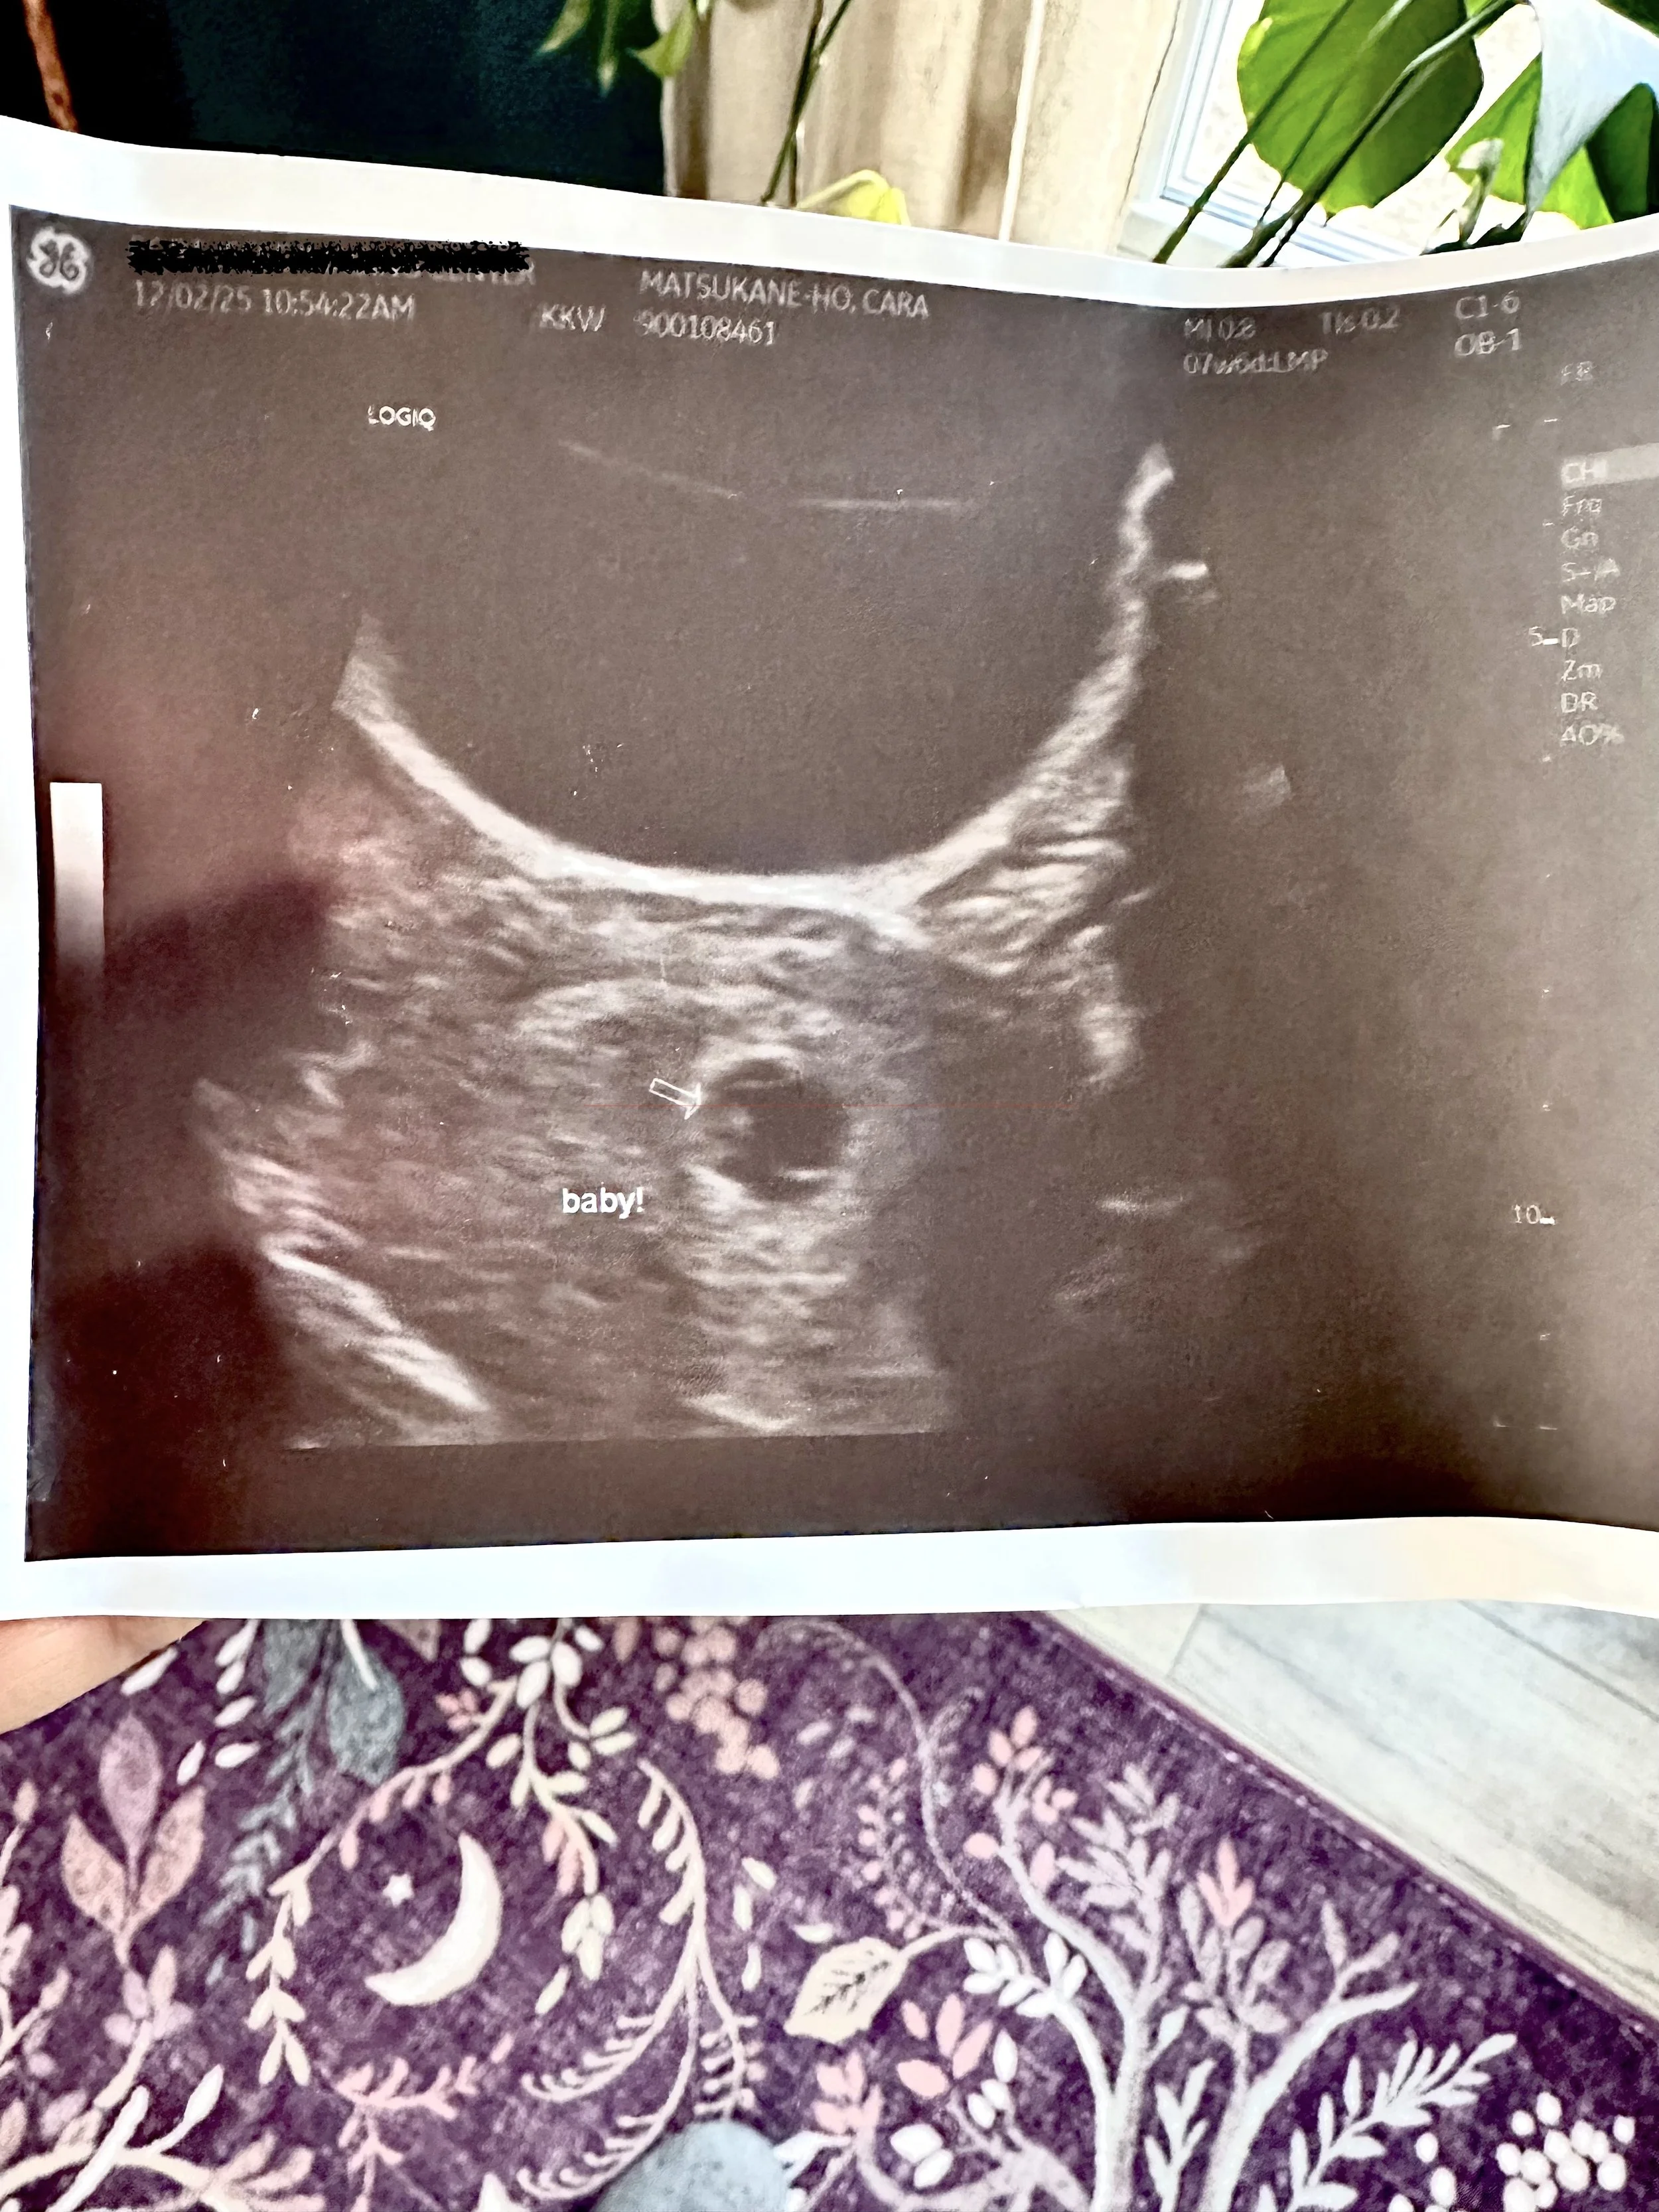

My husband and I went to get our first ultrasound on December 2nd. According to the apps and my midwife, I was supposed to be eight weeks pregnant. We had a student tech do the ultrasound with a mentor coming in to check her work at the end. They made measurements and spoke amongst themselves, and for the most part they acted like my husband and I weren’t even there. Both women were extremely nice and pleasant, but it was clear that a momentous occasion for us was a routine procedure for them.

We got a picture of the baby. I distinctly remember after the ultrasound feeling really disconnected from the baby. I thought I would cry when I saw the ultrasound, like they do on T.V. My husband was moved in a way I couldn’t access. It felt so far away. Looking back, I wonder if deep down I already knew.

We got the results back the next day, and they indicated that the baby was measuring at six weeks, not eight. The heartbeat was on the low side of normal. The yolk sac was on the high side of normal, which can be an indicator for higher risk of miscarriage in the first 12 weeks. Even though my midwife told me to “try not to worry”, I immediately felt anxious. I scheduled another ultrasound for a week later, to check in and see how things were progressing.

We created sacred space: A peace lily and individual flowers which had been sent to us by loved ones, a candle, a quartz crystal in water, copies of the sonogram, and an oracle deck. Brendan also built a fire outside for us to do some burning.

3. We wrote on the back of the sonograms:

4. We took the sonogram and flowers out to the bonfire and burned them together.